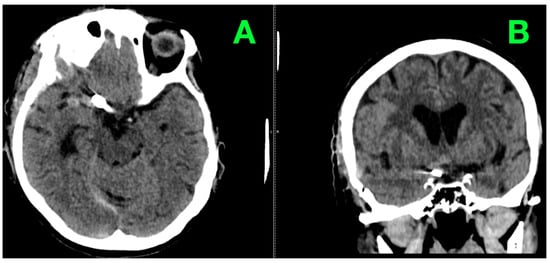

2. Case Presentation